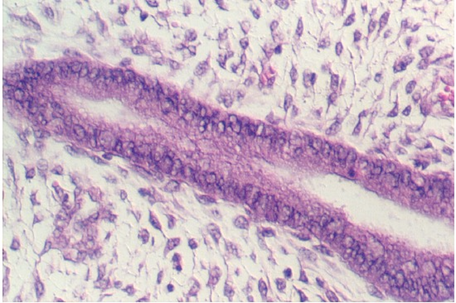

The cervix continues and joins with the vagina. The cervix is lined by simple high columnar epithelium which consists of mucous cells. These are shown in the following views. In the lowest magnification, one can see bundles of smooth muscle in the wall (see below)